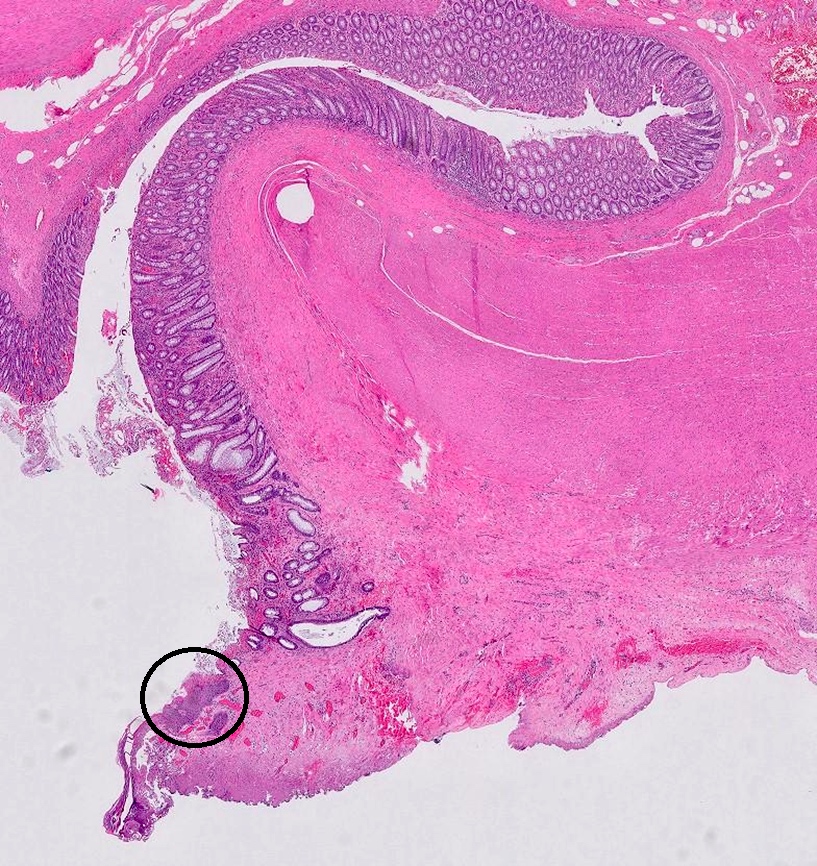

Gross description

- Specimen should be fixed and opened longitudinally for easy sampling of diverticula

- Usually, multiple flask shaped invaginations of colonic wall

- Wall thickening may be present (Surg Endosc 2011;25:2586)

- Narrowing of lumen, shortening of tenia and marked thickening of circular muscle layer may be present (J Clin Gastroenterol 2006;40:S108)

- If it extends deeply, perforation and serosal adhesions may be seen

Gross images

Microscopic (histologic) description

Microscopic (histologic) images

Contributed by Bindu Challa, M.D. and Martha M. Yearsley, M.D.